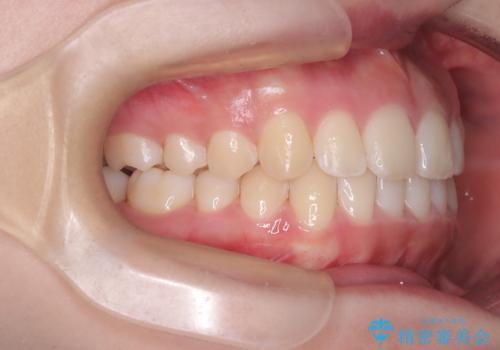

下の前歯のがたつきは解消され、滑らかなアーチ状の歯並びとなりました。

目立たずに治療が進んだことに対しても、患者様から高い満足のお声をいただきました。